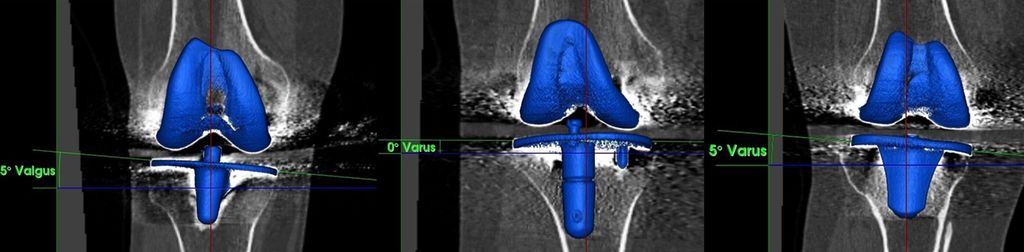

Abb. 4: Koronales Alignment der Tibiakomponente nach konventioneller TKE (gleiches Vorgehen wie in Abb.3)